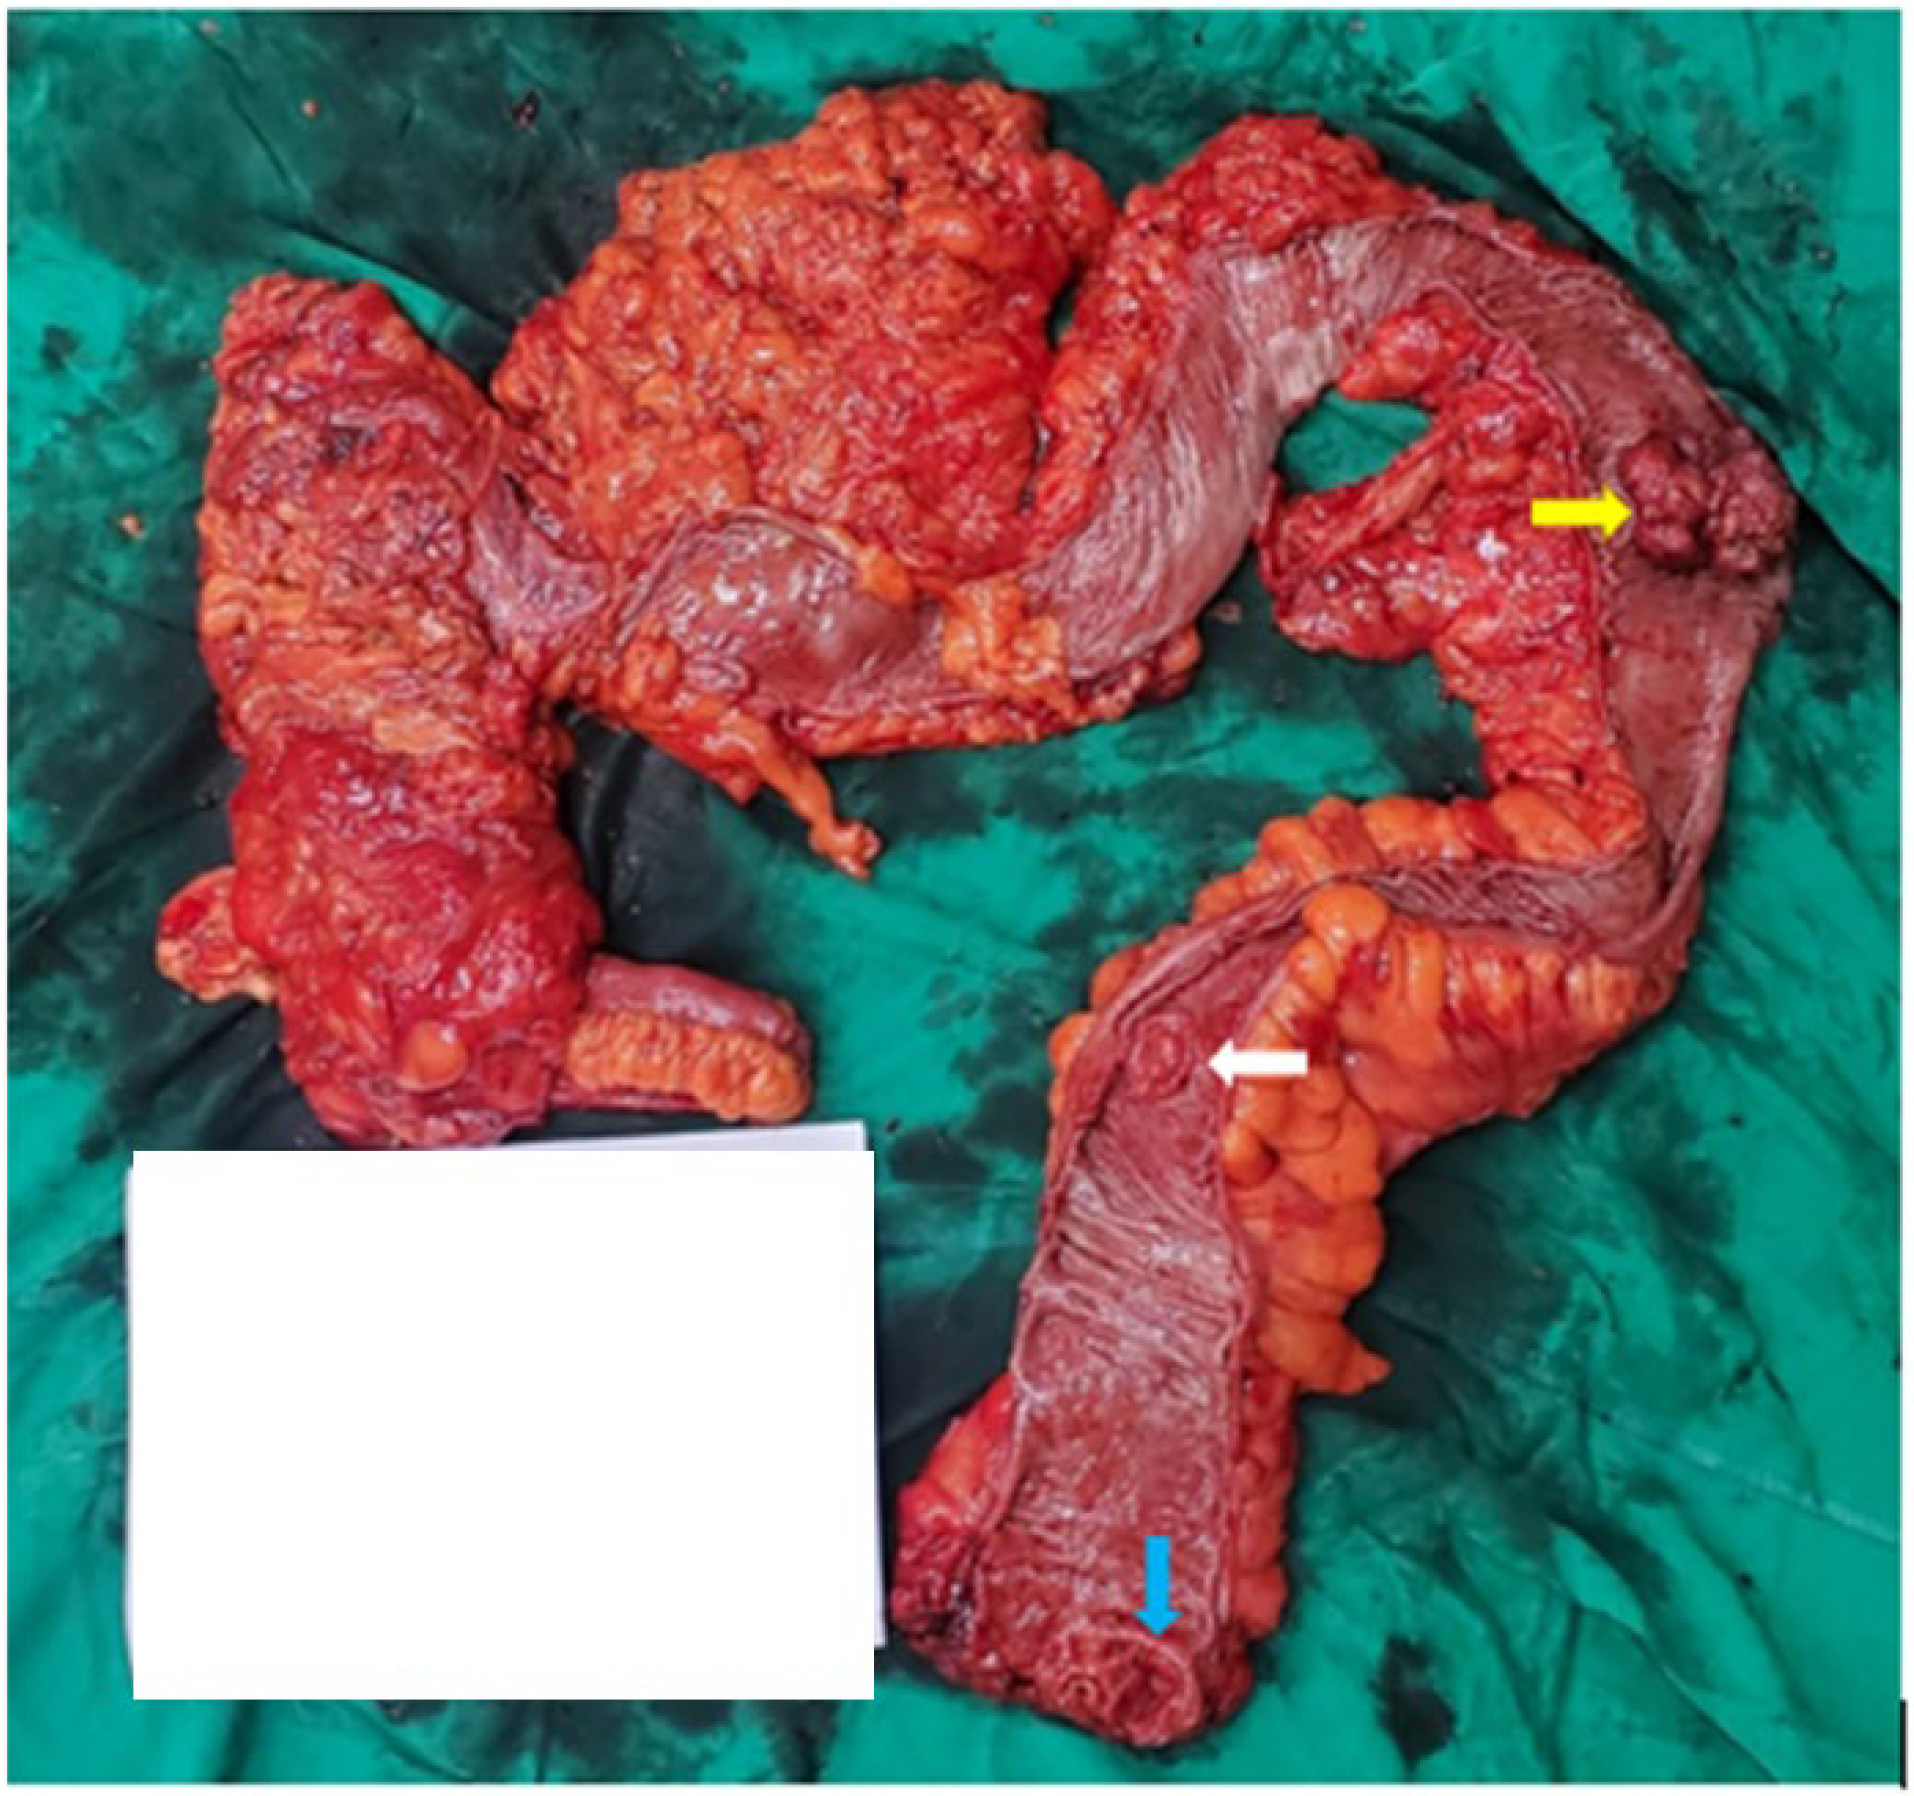

2. Case Presentation